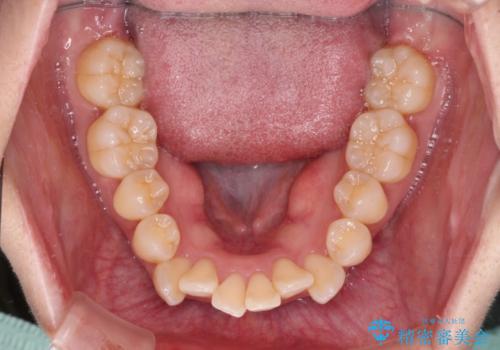

- 前歯の出っ歯と口元の閉じにくさを気にして来院された患者様です。

口元を積極的に引っ込めるために、上下左右の小臼歯4本を抜歯し、目立たないワイヤー装置にて矯正治療を行うこととしました。